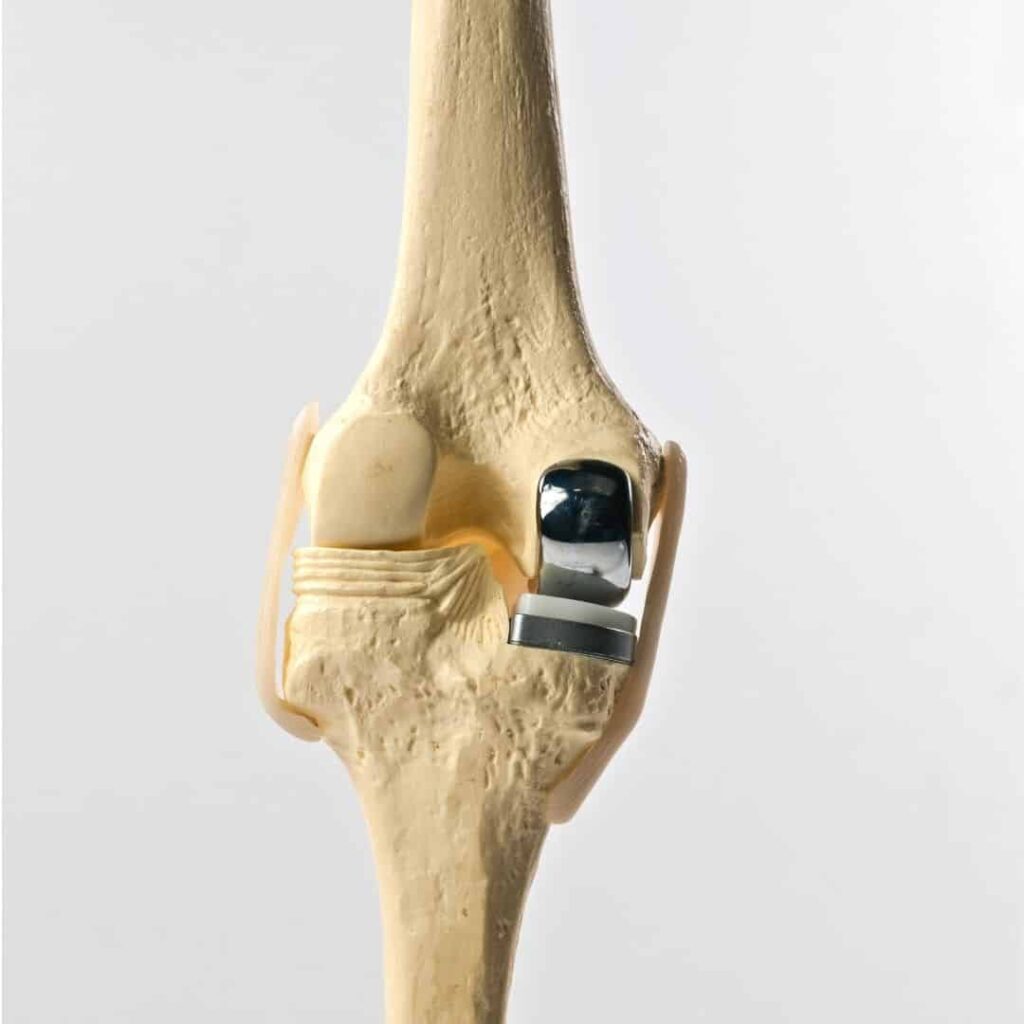

Partial knee replacement (PKR), also known as unicondylar or unicompartmental knee replacement, is a surgical procedure that replaces only the damaged portion of the knee joint, while preserving the healthy parts. Unlike total knee replacement, PKR focuses on restoring function by targeting one or two specific compartments of the knee.